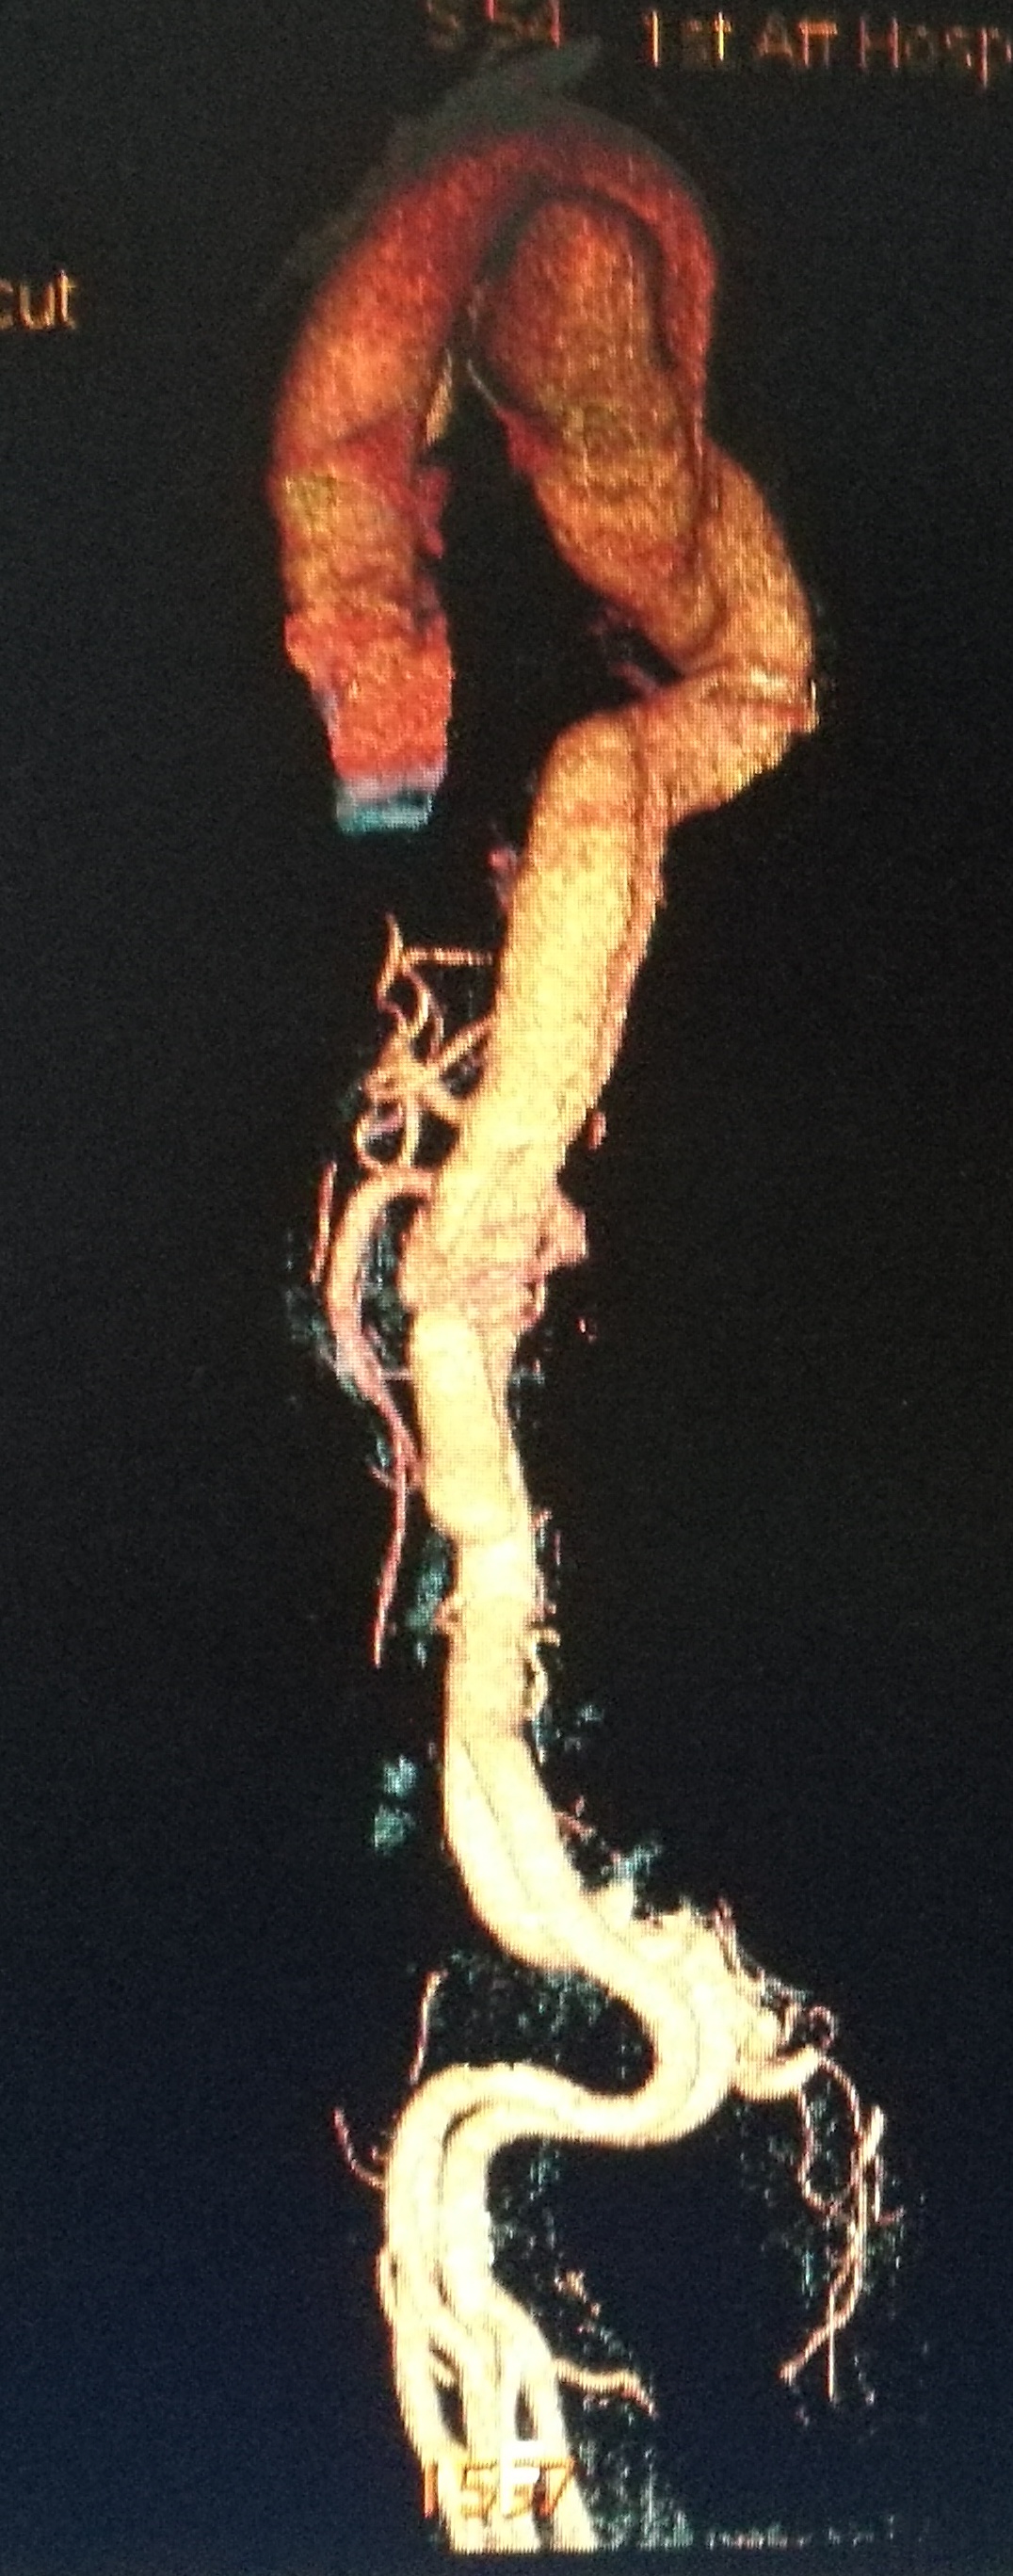

此例患者进行发病时未能确诊,进入慢性期后假腔扩张瘤样变。在CT的部分层面,食道受压看不到。重建影像可见假腔扩张,动脉扭曲。

手术在局麻下进行,经右股动脉穿刺置管到升主,经左桡动脉穿刺植入金标猪尾导管,造影,为确认真假腔,加做右前斜位造影,确认股动脉导管在真腔内,测量后植入覆膜支架。由于扭曲严重(腹主,膈肌附近,弓降),支架最初并未贴服大湾侧,支架送过锁骨下动脉后适当回撤,请拉释放导丝,此时支架整体向大弯侧轻微移动,考虑应力已经得到缓解。完全释放支架,定位良好,封堵完全无内漏。

尽管有加硬导丝,但从二维影像上看,支架并未贴着大弯侧走行